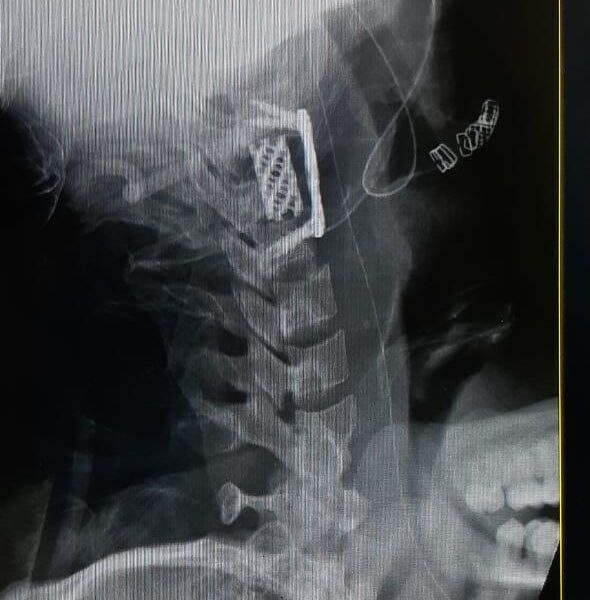

Moments That Mark Meaningful Recovery

Witness real patient transformations at The Ortho Clinic through images that reflect successful treatments and restored mobility.